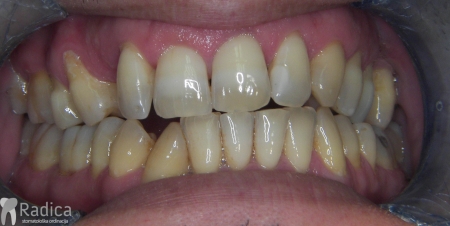

U galeriji slika su prikazani klinički slučajevi ovakvih odraslih pacijenta bilo da se radi samo o ortodontskoj terapiji ili predprotetskoj ortodonciji.

Na sljedećoj slici se mogu vidjeti početak i kraj ortodontske i protetske terapije. Protetske radove radio je dr. Goran Radica.

Na sljedećoj slici mogu se vidjeti početak i kraj ortodontske terapije. Pacijentica je upućena od svog stomatologa nakon što nije bila zadovoljna izgledom osmjeha i odnosom zuba i gingive u privremenom protetskom radu. Napravljena je ortodontska terapija samo u gornjoj čeljusti a nakon toga novi privremeni protetski rad.